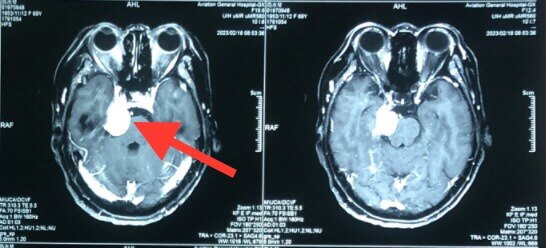

患者69岁女性,入院前10年出现右侧面部麻木,未予重视。2月前出现视物重影,就诊于南通市第一人民医院,2023年2月4日头颅核磁提示:右侧桥小脑角区脑膜瘤可能性大。建议手术治疗。患者及家属为进一步治疗来我科。根据影像学检查考虑脑膜瘤,因肿瘤较大,如不及时手术治疗肿瘤进一步压迫周围神经出现相应临床症状后再次手术,神经功能可能出现不可逆损伤,单纯幕上或幕下单一切口肿瘤全切几率不高,需二次手术治疗,考虑患者高龄手术耐受差,暂行kawase入路切除肿瘤。手术幕上下联合进行手术相对单一入路费用较高,手术风险较大详细向家属介绍手术治疗方案,家属要求幕上入路切除肿瘤。完善术前准备行右侧颞下经岩骨前入路(kawase)中后颅窝占位切除术,显微镜下全切肿瘤,术后患者症状好转出院。

术前